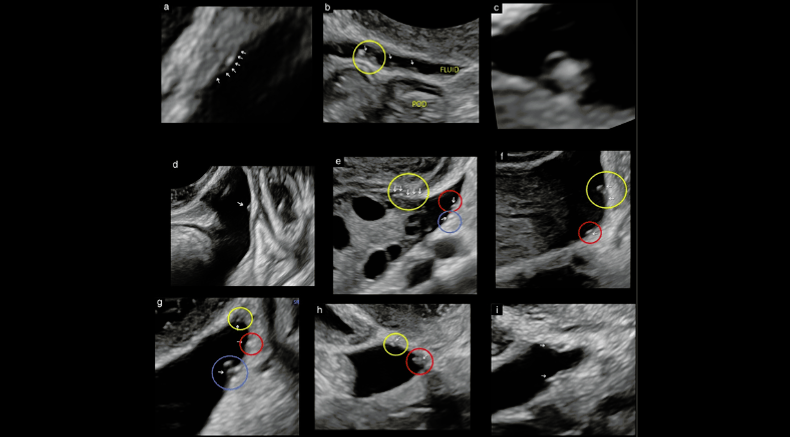

Examples of the ultrasound appearance of superficial endometriosis

Guerriero, S., Condous, G., Rolla, M., Pedrassani, M., Leonardi, M., Hudelist, G., Ferrero, S., Alcazar, J.L., Ajossa, S., Bafort, C., Van Schoubroeck, D., Bourne, T., Van den Bosch, T., Singh, S.S., Abrao, M.S., Di Giovanni, A., Tomassetti, C. and Timmerman, D. (2025), Addendum to consensus opinion